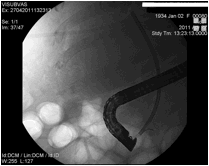

Η ERCP συνήθως διενεργείται σε ασθενείς με γνωστή χοληδοχολιθίαση ή σε εκείνους τους ασθενείς στους οποίους υπάρχει τουλάχιστον μέτρια κλινική υποψία χοληδοχολιθίασης. Στους ασθενείς με χαμηλή κλινική υποψία χοληδοχολιθίασης, προτιμώνται άλλες διαγνωστικές εξετάσεις όπως η MRCP και ο ενδοσκοπικός υπέρηχος, για την ελαχιστοποίηση της πιθανότητας επιπλοκών. Η συνήθης μέθοδος για την απομάκρυνση των λίθων είναι ηενδοσκοπική σφιγκτηροτομή, η οποία επιτρέπει την διάνοιξη του φύματος και την εξαγωγή των λίθων με τη χρήση μπαλονιού ή καλαθιού (basket) προς το δωδεκαδάκτυλο. Εικόνες 1 και 2.

Eικόνα 1: Ασθενής με εναπομείναντα ευμεγέθη           Εικόνα 2:Ασθενής με λιθίαση στη μεσότητα του

λίθο (μαύρο βέλος) στο κατώτερο τμήμα του                           χοληδόχου πόρου (κόκκινο βέλος), καθώς και

χοληδόχου πόρου, μετά από χολοκυστεκτομή –          ευμεγέθη λίθο στον αυχένα της χοληδόχου κύστης

Αφαίρεση με μπαλόνι (λευκό βέλος).                      (μπλε βέλος). Έγινε σφιγκτηροτομή και καθαρισμός του πόρου και την επόμενη ημέρα ο ασθενής υπεβλήθη σε λαπαροσκοπική

χολοκυστεκτομή.